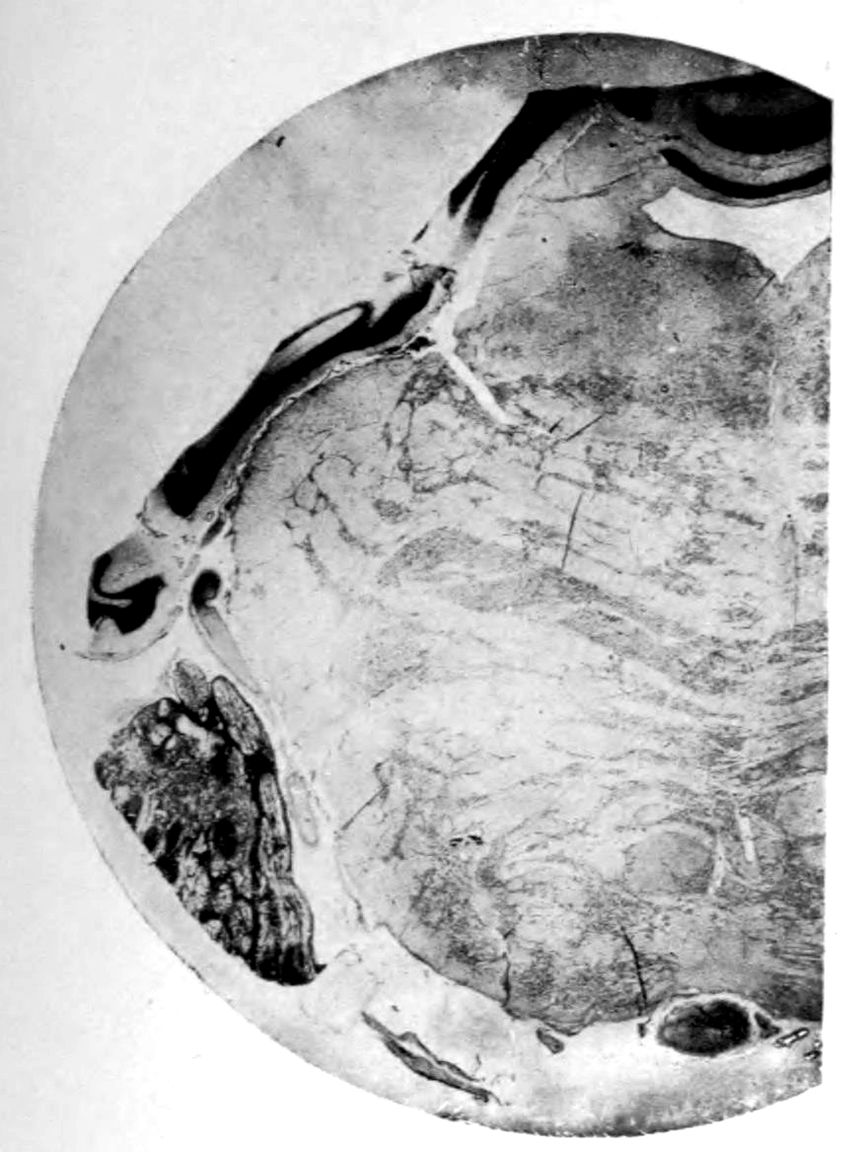

Case I. Spinal Cord (Three Levels) Showing:

A. Marginal sclerosis—effect of old meningitis now extinct.

B. Posterior column sclerosis—effect of meningitis about posterior roots also now extinct.

C. Bilateral pyramidal tract sclerosis—effect of cerebral thrombotic lesions.

Note distortion of tissues in B and C, partly artificial (tissues in places diffluent).